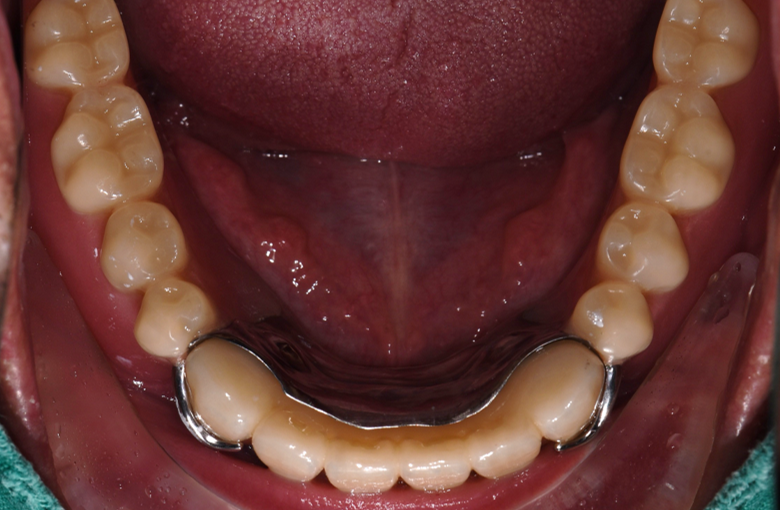

아랫 틀니 똑딱이 연결

80대 환자분으로, 전체틀니를 사용 중이셨는데 아래 틀니가 자주 잇몸에서 떨어져 불편함을 호소하셨습니다.

전체 틀니를 다시 제작하는 방법도 있지만, 최소한의 임플란트로 틀니를 잡아주는 치료를 결정하였습니다. 고령인 점 고려하여 무리가 가지 않게 무절개/최소절개로 4개의 임플란트를 식립하고 임플란트 똑딱이 장치를 이용하여 임플란트와 기존 쓰시던 틀니를 연결하였습니다.

기존에 덜그럭거리던 틀니가 임플란트에 고정되어 씹는 것이 훨씬 수월하다고 하셨습니다.